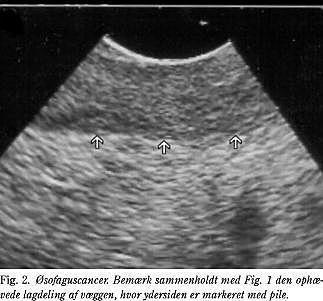

Cancer esophagi

EUS er den undersøgelsesmetode, som er bedst til at stadiebedømme patienter med cancer esophagi (Fig. 2 ), idet denne vurdering dels er afgørende for valg af terapi, dels kan forudsige patientens prognose (6). I en oversigtsartikel er det beskrevet, at T-stadium er korrekt vurderet ved EUS hos 89% af patienterne, mens N-stadium er korrekt vurderet hos 79% (7). Hos ca. 30% af patienterne er det dog ikke muligt at lave en komplet undersøgelse, idet stenose forhindrer passage af ekkoendoskopet. Dette problem kan løses ved at foretage dilatation af øsofagus først og dernæst EUS, eller man kan foretage stadiebedømmelse vha. miniprober, som kan passere stenosen, men sidstnævnte har den ulempe, at de ikke er så præcise ved netop fremskredne tumorer (8). Den sidste løsning ved stenotiske øsofaguscancere er at kombinere fundene ved den inkomplette EUS med andre minimalt invasive undersøgelsesmetoder som laparoskopi og laparoskopisk UL-skanning (LUS), hvilket er vist at være en omkostningseffektiv strategi til at finde patienter med tumorer, som ikke kan fjernes i kurativt øjemed (9). Hos alle patienter med øsofaguscancer, hvor man påtænker kurativt indgreb, bør stadievurdering vha. EUS således indgå i den præoperative vurdering.